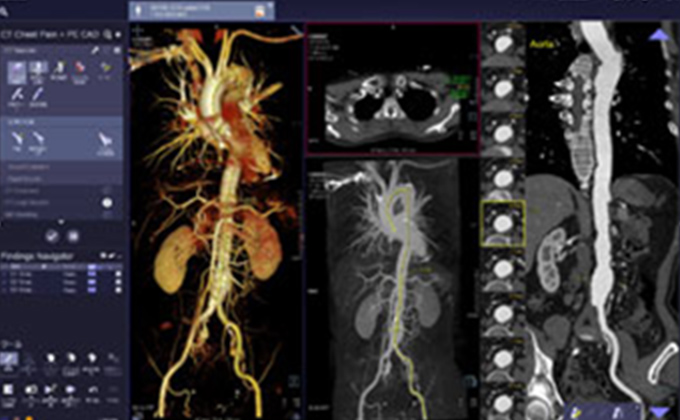

X線とコンピューターを利用して人体の断面画像を撮影する装置で、全身の臓器の形態診断に不可欠な存在となっています。当院のCT装置はエリアディテクターCTと呼ばれる最新の技術が用いられており、広範囲を短時間に撮影する事ができます。検出器1回転が0.275秒での超短時間ボリュームスキャンでスクリーニング検査から救急・精密検査まで、一度の撮影で多くの情報を得ることが可能です。得られた画像から脳血管や心臓血管・骨などの立体的(三次元)表示・解析も可能となっております。また、造影剤を使用することで、より詳しい検査を行う事も可能です。

画像診断支援システム

シーメンス社のSyngo.Viaを導入し、スムーズで的確な読影と、シームレスな画像診断環境の構築を目指しています。

画像提供:シーメンス・ジャパン株式会社